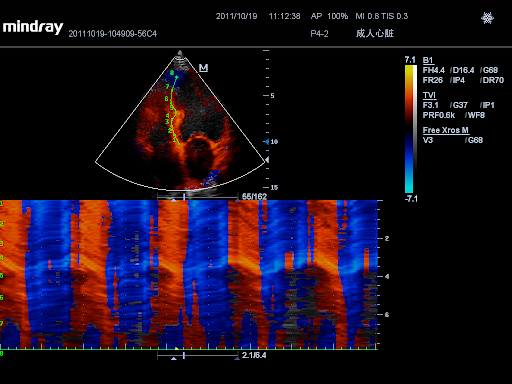

TDI с QA

Тканевая допплеровская визуализация позволяет количественно оценить локальное движение и функцию миокарда, предоставляя полные режимы TDI для более быстрой и прямой диагностики.

Free Xros M

Выполнение точных анатомических измерений с помощью свободно размещаемых линейных шаблонов позволяет достигать оптимального качества изображения за счет одновременного использования до 3 линейных шаблонов.